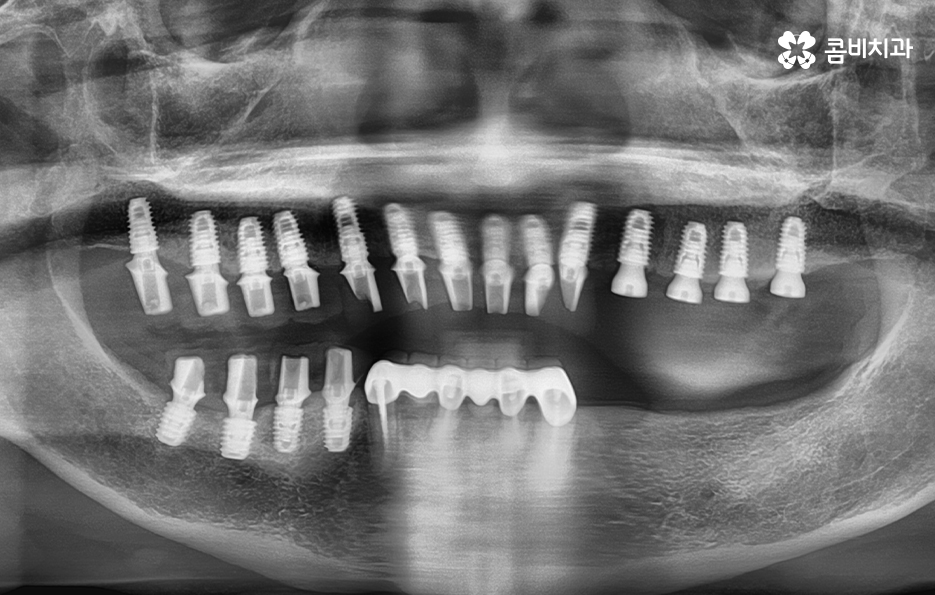

치아의 대부분이 빠지고 아랫니 브릿지만 남아 있는 상태

아랫니는 잇몸이 주저 앉은 상태이며 위의 잇몸과 잇몸뼈의 상태는 비교적 양호한 편

순차적으로 식립이 진행되고 있는 모습